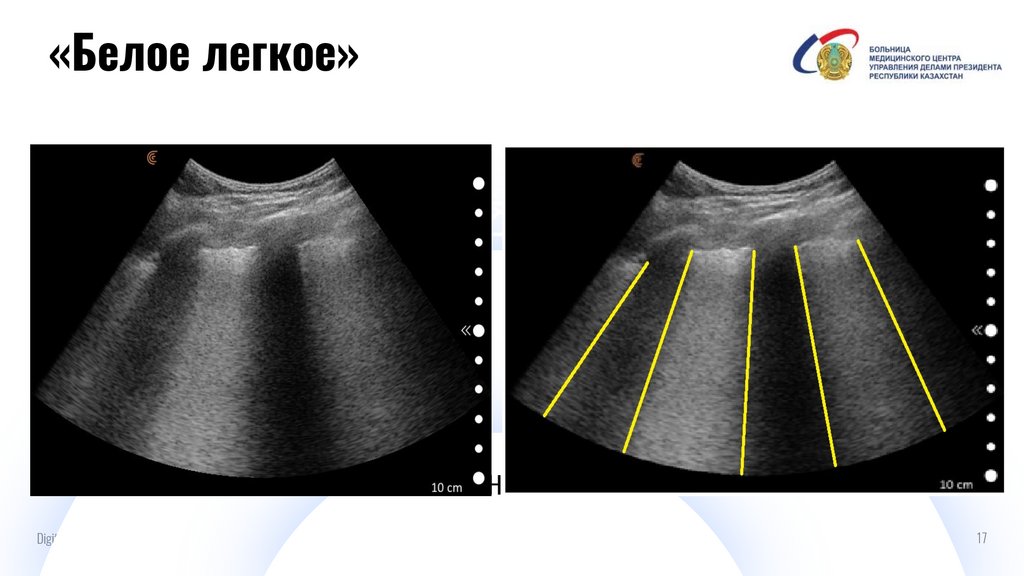

«Белое легкое»

И

А-линии

Digital IT pitch-deck PowerPoint bundle

17